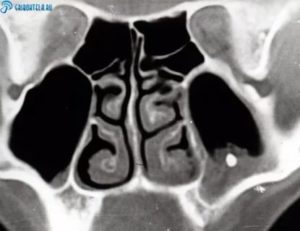

Надежный и информативный диагностический метод. Его эффективность обусловлена внешним видом мицетомы на поздней стадии. В отличие от полипов и раковых клеток, микоз имеет высокую плотность, сравнимую с металлом.

При выведении изображения на томограф, можно заметить объемную шарообразную массу с незначительными структурными изменениями. Плюс метода – полная безопасность для организма, быстрота проведения и возможность использования снимков.

и наиболее информативная методика обнаружения мицетомы — проведение КТ (компьютерная томография). Дело в том, что плотность мицелия аспергилл совпадает с плотностью металла, на получаемых томограммах хорошо виден очаг инфекции. Легко распознать мицелий, который окружён массами, рентгенологическая плотность которых снижена.

Рентгенологическая плотность мицетомы сравнима с плотностью металла. На снимке грибное тело отмечается как яркое пятно, которое окружают массы, менее плотные рентгенологически. Реже грибковый шар определяют при помощи МРТ.